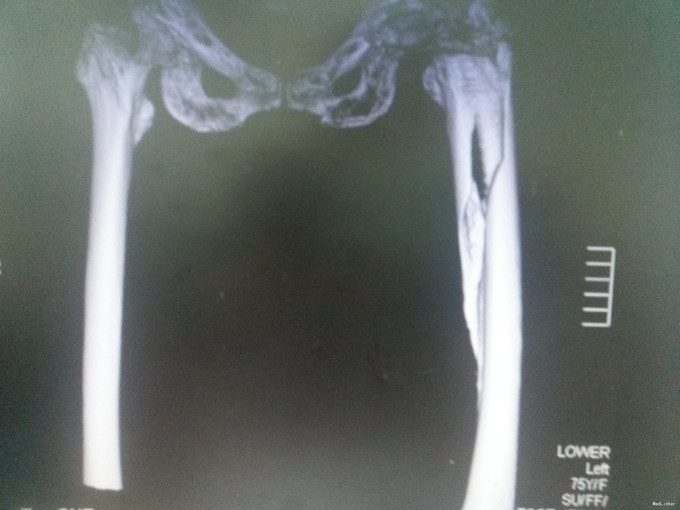

查体:左髋可见一长约8cm的手术疤痕,局部无明显肿胀,左下肢杠力消失,纵向叩击痛(+),肢端血运、感觉及活动良好。 辅助检查:骨盆X片:左股骨假体周围骨折。

诊断:假体周围骨折(左股骨假体柄周围骨折);高血压病;脑梗死后遗症;陈旧性肺结核 治疗:手术治疗[左侧股骨假体取出术+左侧股骨假体周围骨折切开复位钢板钢缆内固定术(zimmer)+左侧股骨假体置入术(MP,Link)] 术中探查及处理:股骨大粗隆崩裂,骨折线自近端向远端延伸至股骨中段,呈螺旋形,骨折块粉碎,移位明显。骨折断端可见淤血块。顺利取出假体柄后,复位骨折块,予复位钳临时固定后,予钢板钢缆(zimmer)加压捆扎。待骨折固定牢靠后,按照髋关节置换流程逐步扩髓,最后选择25omm长的14号假体(MP,Link)安装,36mm标准颈股骨头复位。测试各方向活动良好,松紧度合适。